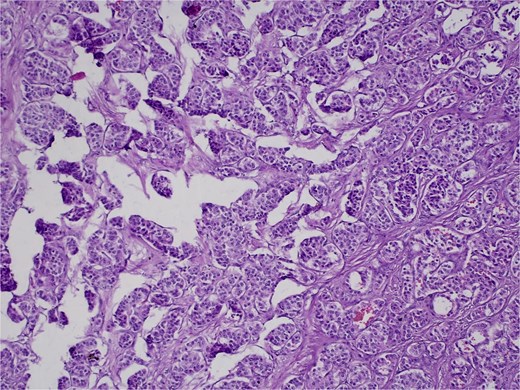

On 27 January 2025, the patient underwent a Whipple procedure (pancreaticoduodenectomy). The surgery included cephalic pancreatectomy with reconstruction through hepaticojejunostomy and gastrojejunostomy in a Roux-en-Y configuration. Gross pathology revealed a firm, white-yellow, indurated mass in the pancreatic head measuring 3.7 × 3.5 × 3 cm with irregular borders and central hardness (Fig. 4). Histopathological analysis confirmed a Grade 1 neuroendocrine tumor (insulinoma), with a Ki-67 index of 2%. The tumor showed direct extension to adjacent pancreatic tissue, the duodenal muscularis propria, the adventitia, and the muscularis of the common bile duct. Five peripancreatic lymph nodes were dissected, three of which were positive for metastases (Figs 5–9).

H&E stain, 100× magnification. Irregular clusters of neoplastic cells with vascular invasion.